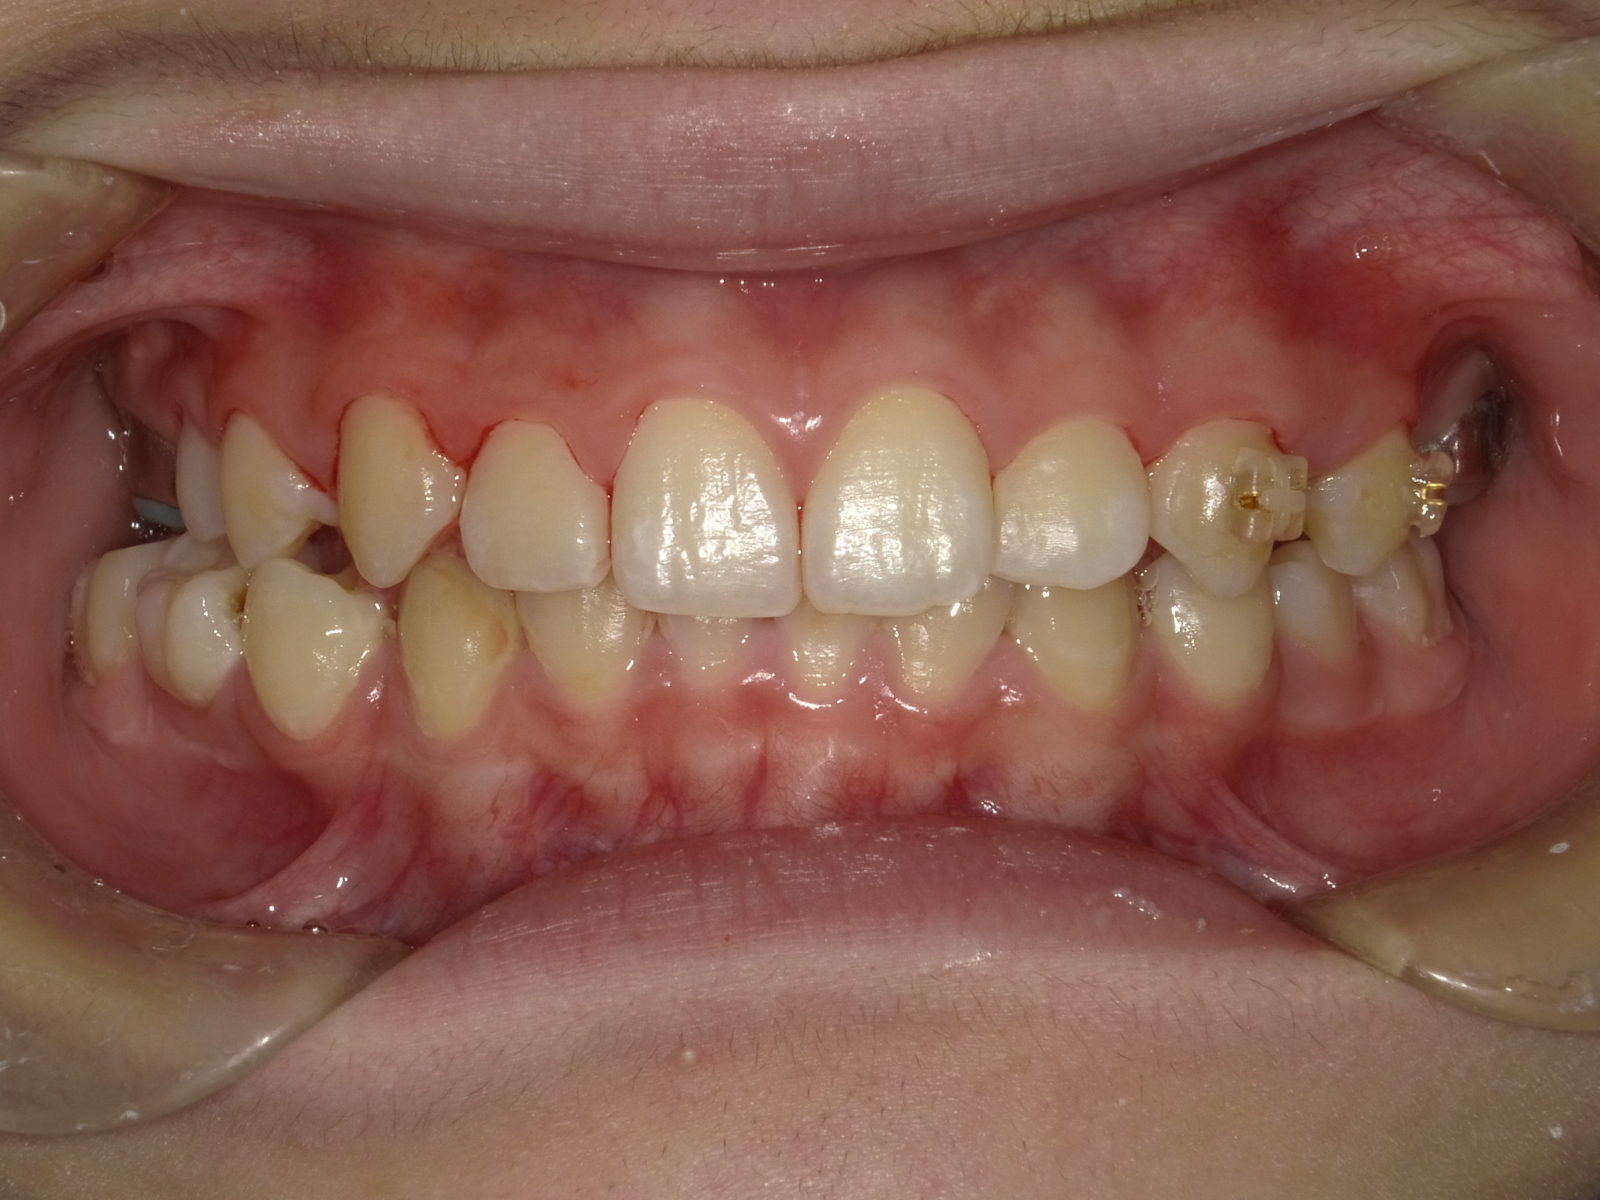

顎顔面矯正も「顎のスペースを広げるアプローチ」を行う矯正手法ですが、床矯正のデメリットをすべて改善しています。その他、次のようなメリットも期待できる矯正治療です。

顎顔面矯正は一般的な矯正と異なり「顎を拡大」するのですが、特に「上の顎」を拡大することが大きな特徴です。これを行うことで、先ほどのメリットが副次的効果として生まれます。

逆に、「上の顎が狭い/未発達」なままだと次のような流れで様々な問題が生じます。

①上顎の狭さは鼻腔の狭さにも比例するため、鼻呼吸がしづらい